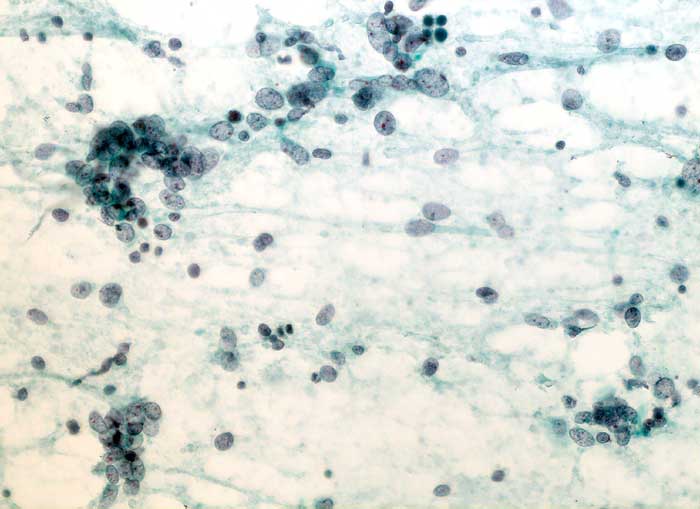

Adenosarkom

maligner Tumor

Uterus

Uterus, Frischgewebsausstriche: Zahlreiche vielfach nacktkernige Zellen eines teils spindelzelligen malignen Tumors. Die Spindelzellen sind sehr unterschiedlich gross. Die Kerne sind längsoval, hyperchromatisch und weisen einen oder mehrere Nukleolen auf. Die Zellen liegen einzeln oder zu kleinen Gruppen zusammengeballt. Detritischer Hintergrund.

Zytologische Diagnose: Zahlreiche Zellen eines teils spindelzelligen malignen Tumors.

Der spindelzellige, teils deutlich sarkomatoide Aspekt spricht am ehesten für einen malignen Mischtumor.